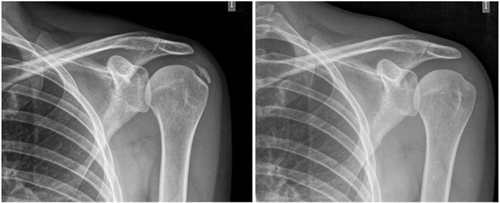

Figure 1

Figure 2

Table I

Figure 3

Figure 4

Figure 5

Figure 6